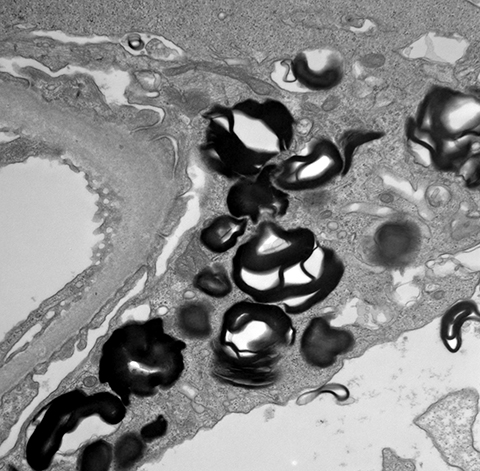

Podocyte myelin figures in Fabry disease